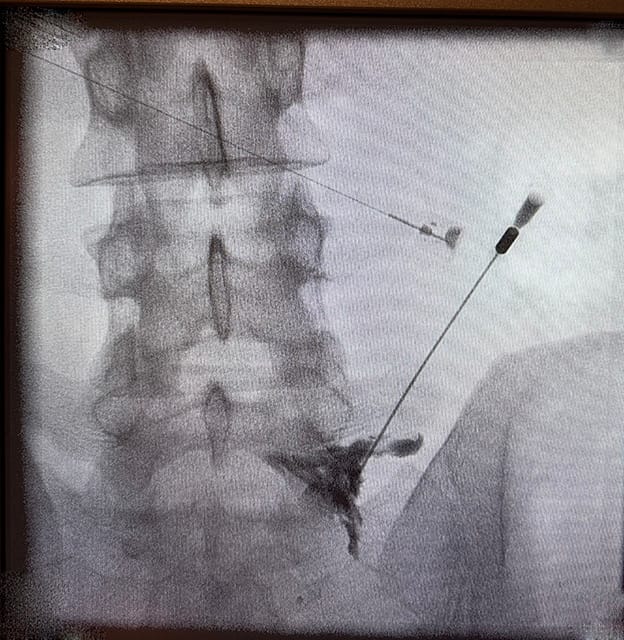

İşlemi tam teşekküllü ameliyathane koşullarında gerçekleştiriyoruz. Uygulama sırasında gelişmiş C-kollu skopi (X-ışını) cihazları kullanıyoruz. Hastayı uyutmaya gerek duymuyoruz. Sadece uygulama bölgesini lokal anestezi ile uyuşturuyoruz.

Önce skopi cihazı ile ağrıya neden olan siniri milimetrik olarak belirliyoruz. Ardından özel bir iğne ile bu sinirin etrafına ilaç kombinasyonu enjekte ediyoruz. Son aşamada ise kontrast madde kullanarak ilacın doğru yere yayıldığını teyit ediyoruz.